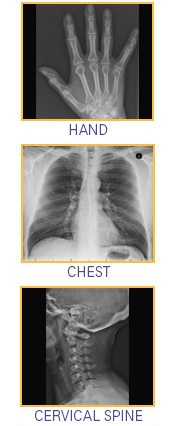

X-ray (Radiography) Services

• Head

• Neck

• Chest

• Spine

• Abdomen

• Pelvis

• Joint

• Extremities